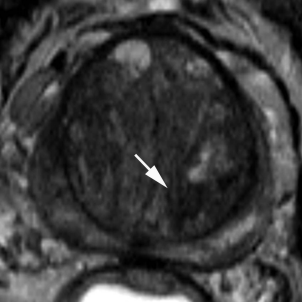

PIRADS 3

Heterogeneous signal intensity with obscured margins (arrow). Includes others that do not qualify as 2, 4, or 5.